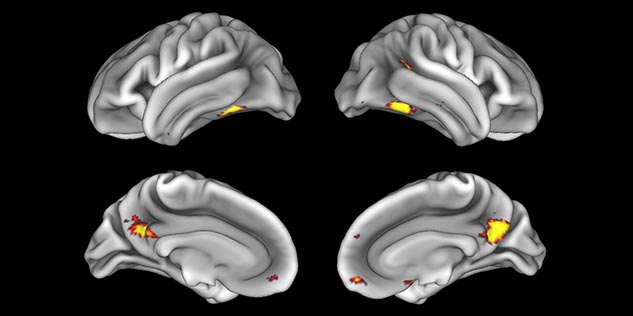

fMRI of viewing and matching facial expressions

BOLD fMRI activation, depicted in color, of left anterior insula (MNI plane z = 8 mm) in a single subject by a contrast between viewing and matching faces with negative emotion (angry, sad, scared) versus happy faces. The voxelwise threshold is p < 0.001, and colored voxels survive false discovery rate correction to p < 0.05. The activated voxels in color are overlaid on the subject's own 3D-TFE image displayed in grayscale, after transforming the data to MNI space. The fMRI pulse sequence was a single shot FFE echo planar acquisition using MultiBand SENSE factor 6, dS SENSE factor 1, isotropic voxel size 2.4 mm, 60 transverse slices, TR 950 ms, TE 30 ms, flip angle 52 degrees, 517 dynamic scans, total scan duration 8:21 minutes. Image provided by James M. Bjork, PhD, Associate Professor of Psychiatry at VCU.

fMRI test of faces and places

Emotional n-back task combines a test of working memory with the use of emotive (faces) and neutral (places) images. The contrast in the images is between the activity when faces are presented compared to places, showing activation in the amygdala, fusiform, and occipital face areas.

Processing based on the Human Connectome Project (HCP) pipelines. The high resolution of the fMRI data allows extraction of the cortical surface, with minimal averaging of non-cortical signal. Surface based analysis provides improved cross-subject alignment, and prevents signal contamination between adjacent sulci.

Group analysis of 88 9- and 10-year olds part of ABCD, all scanned at UVM on Philips Achieva 3.0T dStream. Scale runs from red p=0.001 to yellow p<10ˆ-5. Images provided by Dr. Watts.

Acquisition using the ABCD protocol for fMRI with TR 800 ms, TE 30 ms, flip angle 52°, 2.4 mm isotropic imaging resolution with a 216×216×144 mm3 field of view using a MultiBand acceleration factor of 6 (60 slices, no gap). Two runs of 5 minutes per subject.